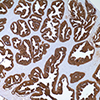

Prostate-Specific Antigen (PSA) is a 33 kDa protein primarily produced by the prostatic epithelium and the epithelial lining of the periurethral glands 1. PSA is strongly expressed in both normal and neoplastic prostatic tissue. Although PSA can be considered prostate-specific, PSA and/or PSA gene expression has been detected at low levels in some extra-prostatic tissues such as normal breast tissue, breast tumors, endometrium, adrenal neoplasms and renal cell carcinomas 1, 2, 3. Anti-PSA is most useful in determining the prostatic origin of carcinomas in non-prostate tissues (metastatic disease) using IHC techniques. This product is best used in conjunction with a panel of antibodies as, up to 27% of prostate carcinoma cases (predominantly poorly differentiated carcinomas) can be negative for this marker.